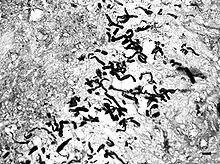

Pythiosis is suspected to be heavily underdiagnosed due to unfamiliarity with the disease, the rapid progression and morbidity, and the difficulty in making a diagnosis. Symptoms often appear once the disease has progressed to the point where treatments are less effective. As the organism is neither a bacterium, virus, nor fungus, routine tests often fail to diagnose it. In cytology and histology, the organism does not stain using Giemsa, H&E, or Diff-Quick, but the hyphae are outlined by surrounding tissue. GMS staining is required to identify the hyphae in slides, and highlights the lack of septation which helps distinguish the organism from fungal hyphae. Granulomatous inflammation with numerous eosinophils is suggestive that the hyphae are oomycetes rather than fungi, which are less likely to attract eosinophils. The symptoms are usually nonspecific and the disease may not be included in a differential diagnosis in human medicine, though it is familiar to veterinarians.